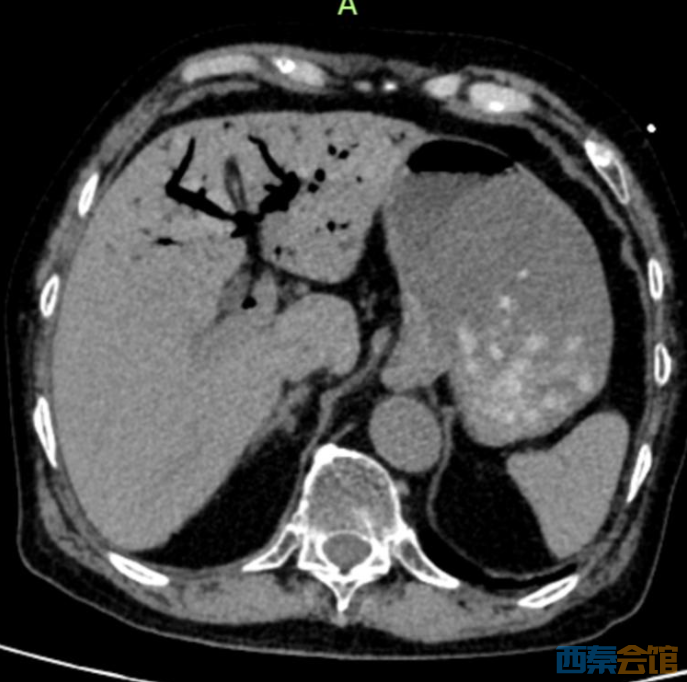

平时的剩菜、剩饭,一些人舍不得倒,习惯放冰箱里,到时候“热一热再吃”。但冰箱不是食物保险箱,食物保存不当或者放久了食用,会致病,甚至会危及生命。 近日,临海市第二人民医院ICU接诊一位76岁患者,只因吃了冰箱冷藏4天的鸡肉,突发休克、肝脏里布满气体,被医生判定为“死神之征”。 凶险急症: 肝门静脉积气 医学上的“死神之征” 当晚10点,76岁李大伯被家人紧急送入临海市第二人民医院急诊,他大汗淋漓、腹部僵硬如石。据家人说,李大伯从下午4点开始腹胀腹痛,症状持续加重。 急诊CT结果让医护人员高度警惕:肝门静脉及肠系膜静脉广泛积气。

肝脏内血管广泛积气